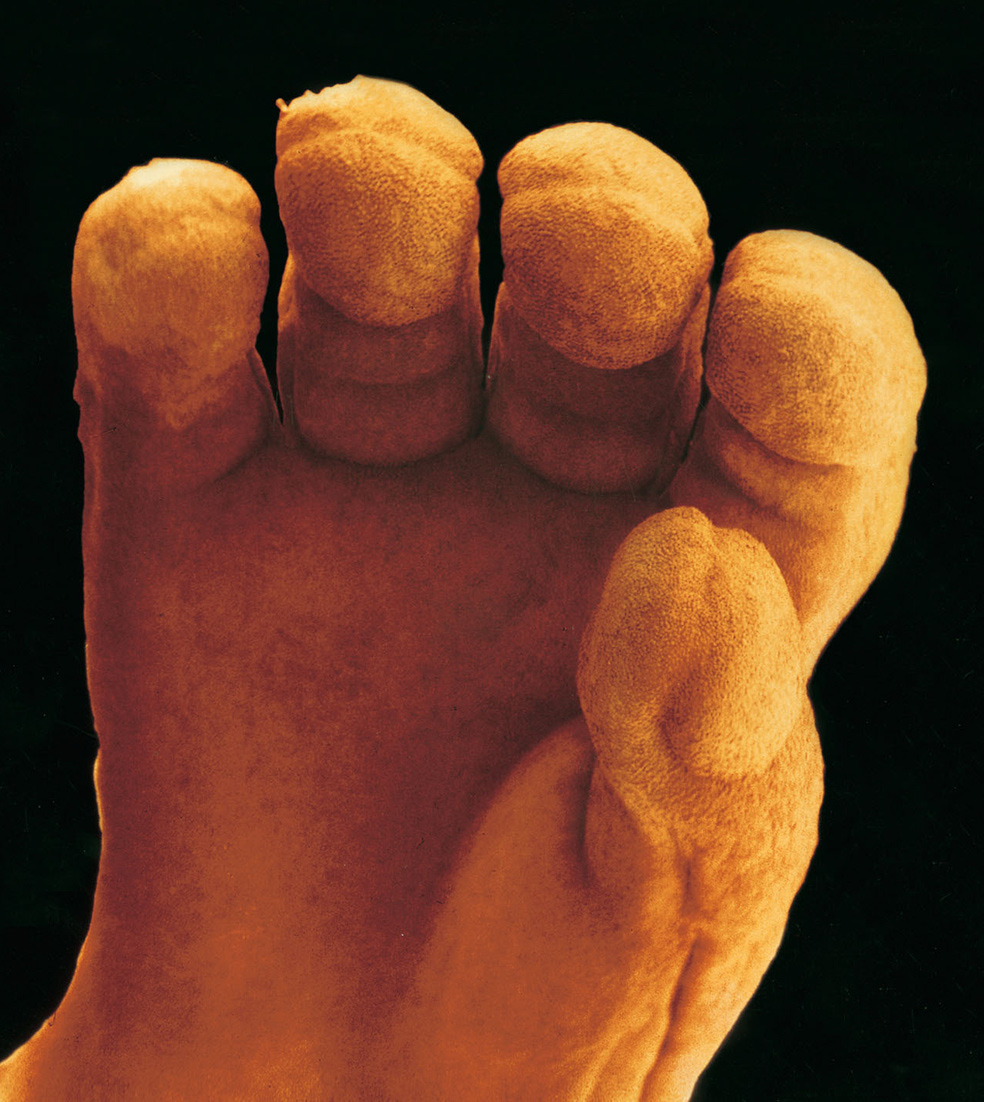

Las líneas del destino

11 semanas: surgen los dedos con sus huellas dactilares. «Esta mano me recuerda a la agrietada piel de un esforzado trabajador manual», aseguraba Nilsson. Todos los órganos del cuerpo están ya ubicados en el que será su lugar definitivo. El feto mide cinco centímetros.